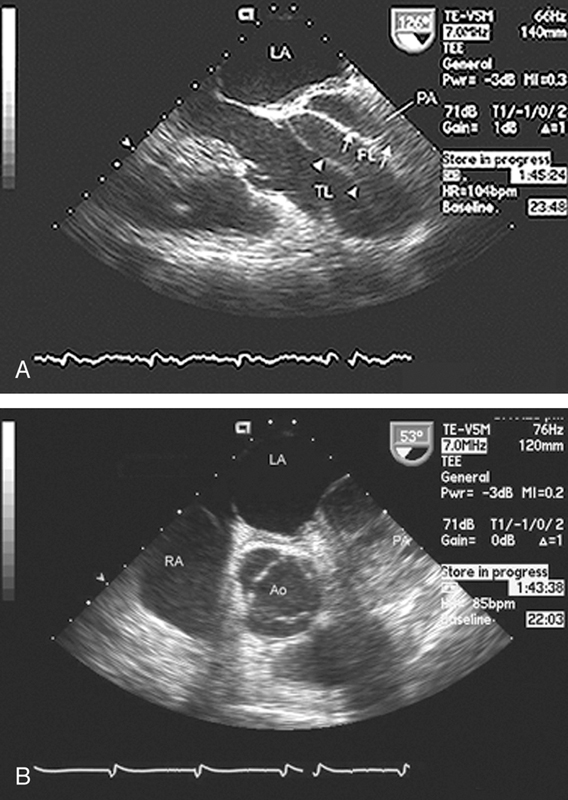

فحوصات تشخيصية لبعض امراض القلب والشرايين التاجية